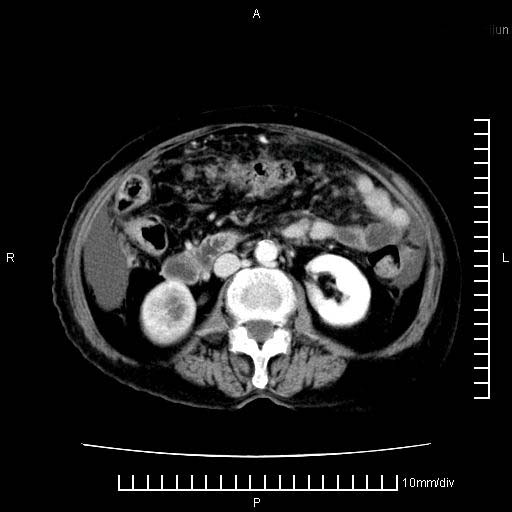

上腹疼痛月余,外院核磁诊断胰腺癌。现临床示右下腹可明显触及包块,可片子上怎么没有看到?

1.胰腺颈体部癌。

2。腹腔积液。

3。右胸腔积液,伴右肺下叶部分萎陷。

4。右肾盂囊肿。

胰腺体部癌累及周围器官,腹膜、粘连

1。胰腺ca伴腹膜腔转移

2。肝左叶低密度灶,考虑转移可能

胰腺体部癌累及周围器官,腹膜、粘连,临床摸到的可能是粘的组织

胰腺结构模糊,胰尾部见囊性包块,周围脂肪密度增高,左肾前筋膜增厚,胸水、腹水。不符合胰腺ca伴腹膜腔转移。考虑胰腺炎伴假性囊肿形成、胸腹腔积液。

右肾盂囊肿。

1)考虑胰腺癌并胰腺假性囊肿形成。2)肝内低密度灶,不排除转移。3)右肾盂积水。4)腹水。5)右侧胸腔积液并右肺下叶部分膨胀不全。